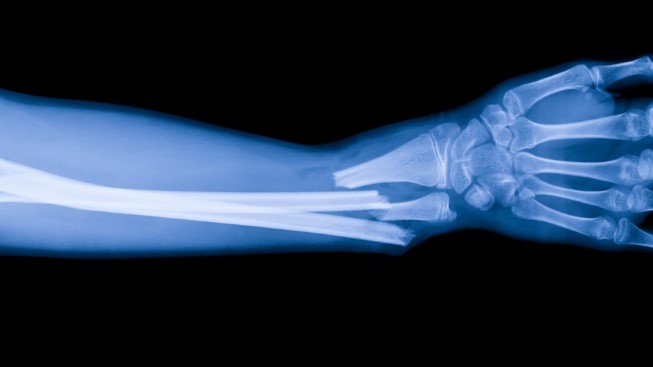

Toch zagen de spoedposten zagen de nodige pols-, enkels- en heupfracturen. Het LUMC heeft extra mensen ingezet, vooral op de gipskamer. Al bleek dat in de loop van de middag niet echt nodig.

Het ANP meldde extra botbreuken in het Dijklander Ziekenhuis in Hoorn en Purmerend, Tergooi MC in Hilversum. Ook in het OLVG kwamen er meer mensen met botbreuken binnen. In het Jeroen Bosch Ziekenhuis in Den Bosch is het maandag drukker dan op een gewone maandag, door gladheid en sneeuw. Het ziekenhuis behandelde maandagochtend veertien mensen die waren uitgegleden, terwijl er normaal gesproken hooguit een paar mensen komen, meldt het ANP.

Het Martini Ziekenhuis in Groningen en het Meander MC in Amersfoort zagen beide minder dan tien botbreuken die veroorzaakt werden door de gladheid.